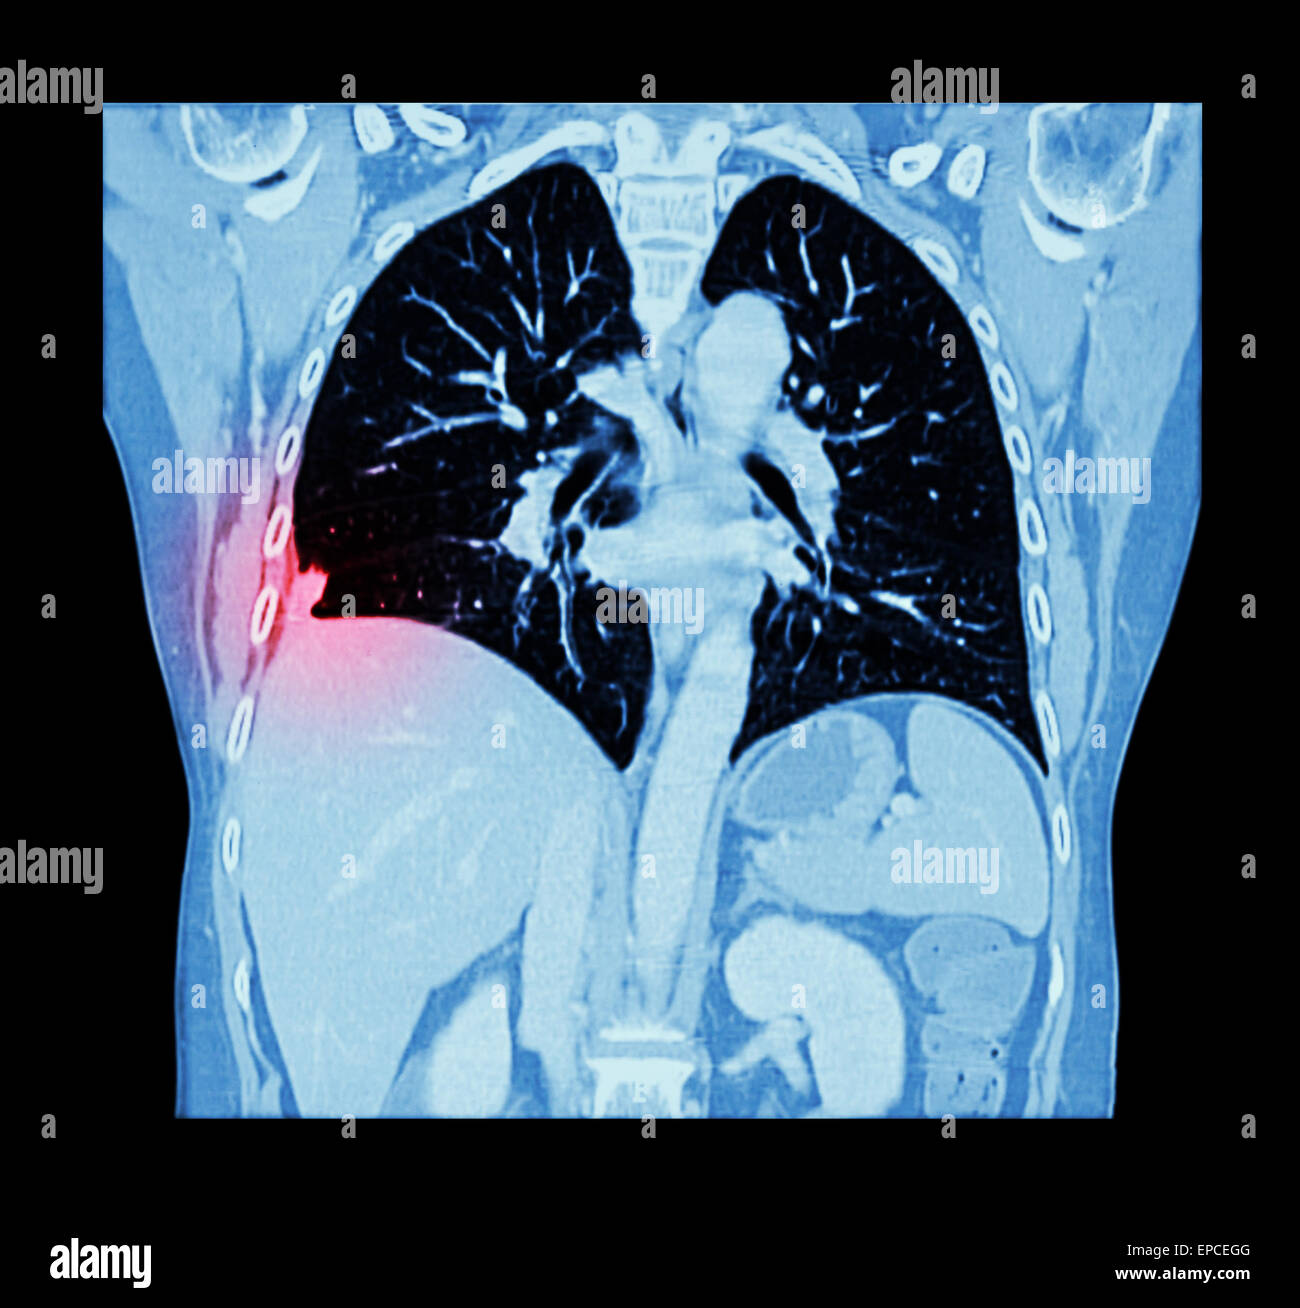

Lung cancer ( CT scan of chest and abdomen show right lung cancer Would A Vq Scan Show Lung Cancer a vq scan is short for lung or pulmonary ventilation (v) and perfusion (q) scans. a v/q scan is most often used to check for a pulmonary embolism (pe). It helps us to diagnose lung conditions. It may also be used to: Find problems with blood flow in the. a vq scan looks at the air supply. Would A Vq Scan Show Lung Cancer.